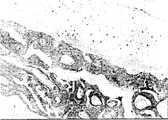

图1是本发明软骨细胞复合皮质骨BMG培养6天的切片HE染色图,10X;Fig. 1 is the slice HE staining figure that chondrocyte composite cortical bone BMG of the present invention is cultivated for 6 days, 10X;

按照本发明的制备方法制得的工程软骨,参见图1,2,种植于BMG的软骨细胞培养6d形成细胞薄层;参见图3、4,培养12d形成8~10层细胞的类软骨组织,细胞周围氨基多糖染色明显;参见图5、6、7、8,培养18d形成12~15层细胞的类软骨组织,细胞周围氨基多糖染色更明显并出现胶原成分;参见图9、10,培养到24d直至42d形成20层以上细胞的类软骨组织。不同的是,培养在皮质骨BMG形成的类软骨组织围绕于BMG表面,类似于关节表面软骨;培养在松质骨BMG形成的类软骨组织,细胞分布于松质骨BMG网眼中形成浑然一体。According to the engineered cartilage prepared by the preparation method of the present invention, see Figures 1 and 2, the chondrocytes planted in the BMG are cultured for 6 days to form a thin layer of cells; see Figures 3 and 4, the cartilage-like tissue with 8 to 10 layers of cells is formed after being cultivated for 12 days, The staining of amino polysaccharides around the cells is obvious; see Figures 5, 6, 7, and 8, cartilage-like tissue with 12 to 15 layers of cells is formed after 18 days of culture, and the staining of amino polysaccharides around the cells is more obvious and collagen components appear; see Figures 9 and 10, cultured to From 24d to 42d, cartilage-like tissue with more than 20 layers of cells was formed. The difference is that the cartilage-like tissue cultured on cortical bone BMG surrounds the BMG surface, similar to articular surface cartilage; the cartilage-like tissue cultured on cancellous bone BMG has cells distributed in the mesh of cancellous bone BMG to form a seamless body.